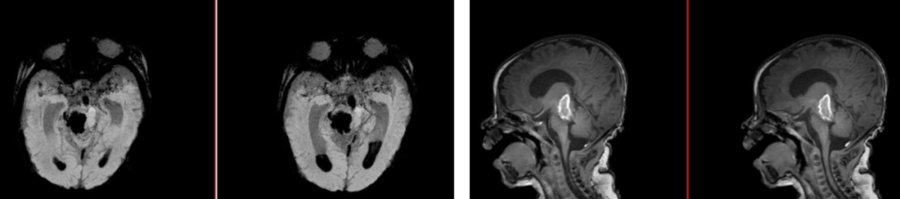

颅脑CT提示脑干、丘脑出血破入脑室

经过新生儿重症监护室积极治疗后,甜甜的病情暂时趋于稳定,但颅脑MRI及CTA检查结果显示情况不容乐观,脑干、丘脑出血破入脑室。虽然血肿使组织结构不易辨清,但经验丰富的王广宇仍从影像学上“嗅出”了异常。磁共振及CTA检查结合临床,考虑“脑干海绵状血管瘤出血”。

颅脑MRI及SWI考虑脑干海绵状血管瘤出血